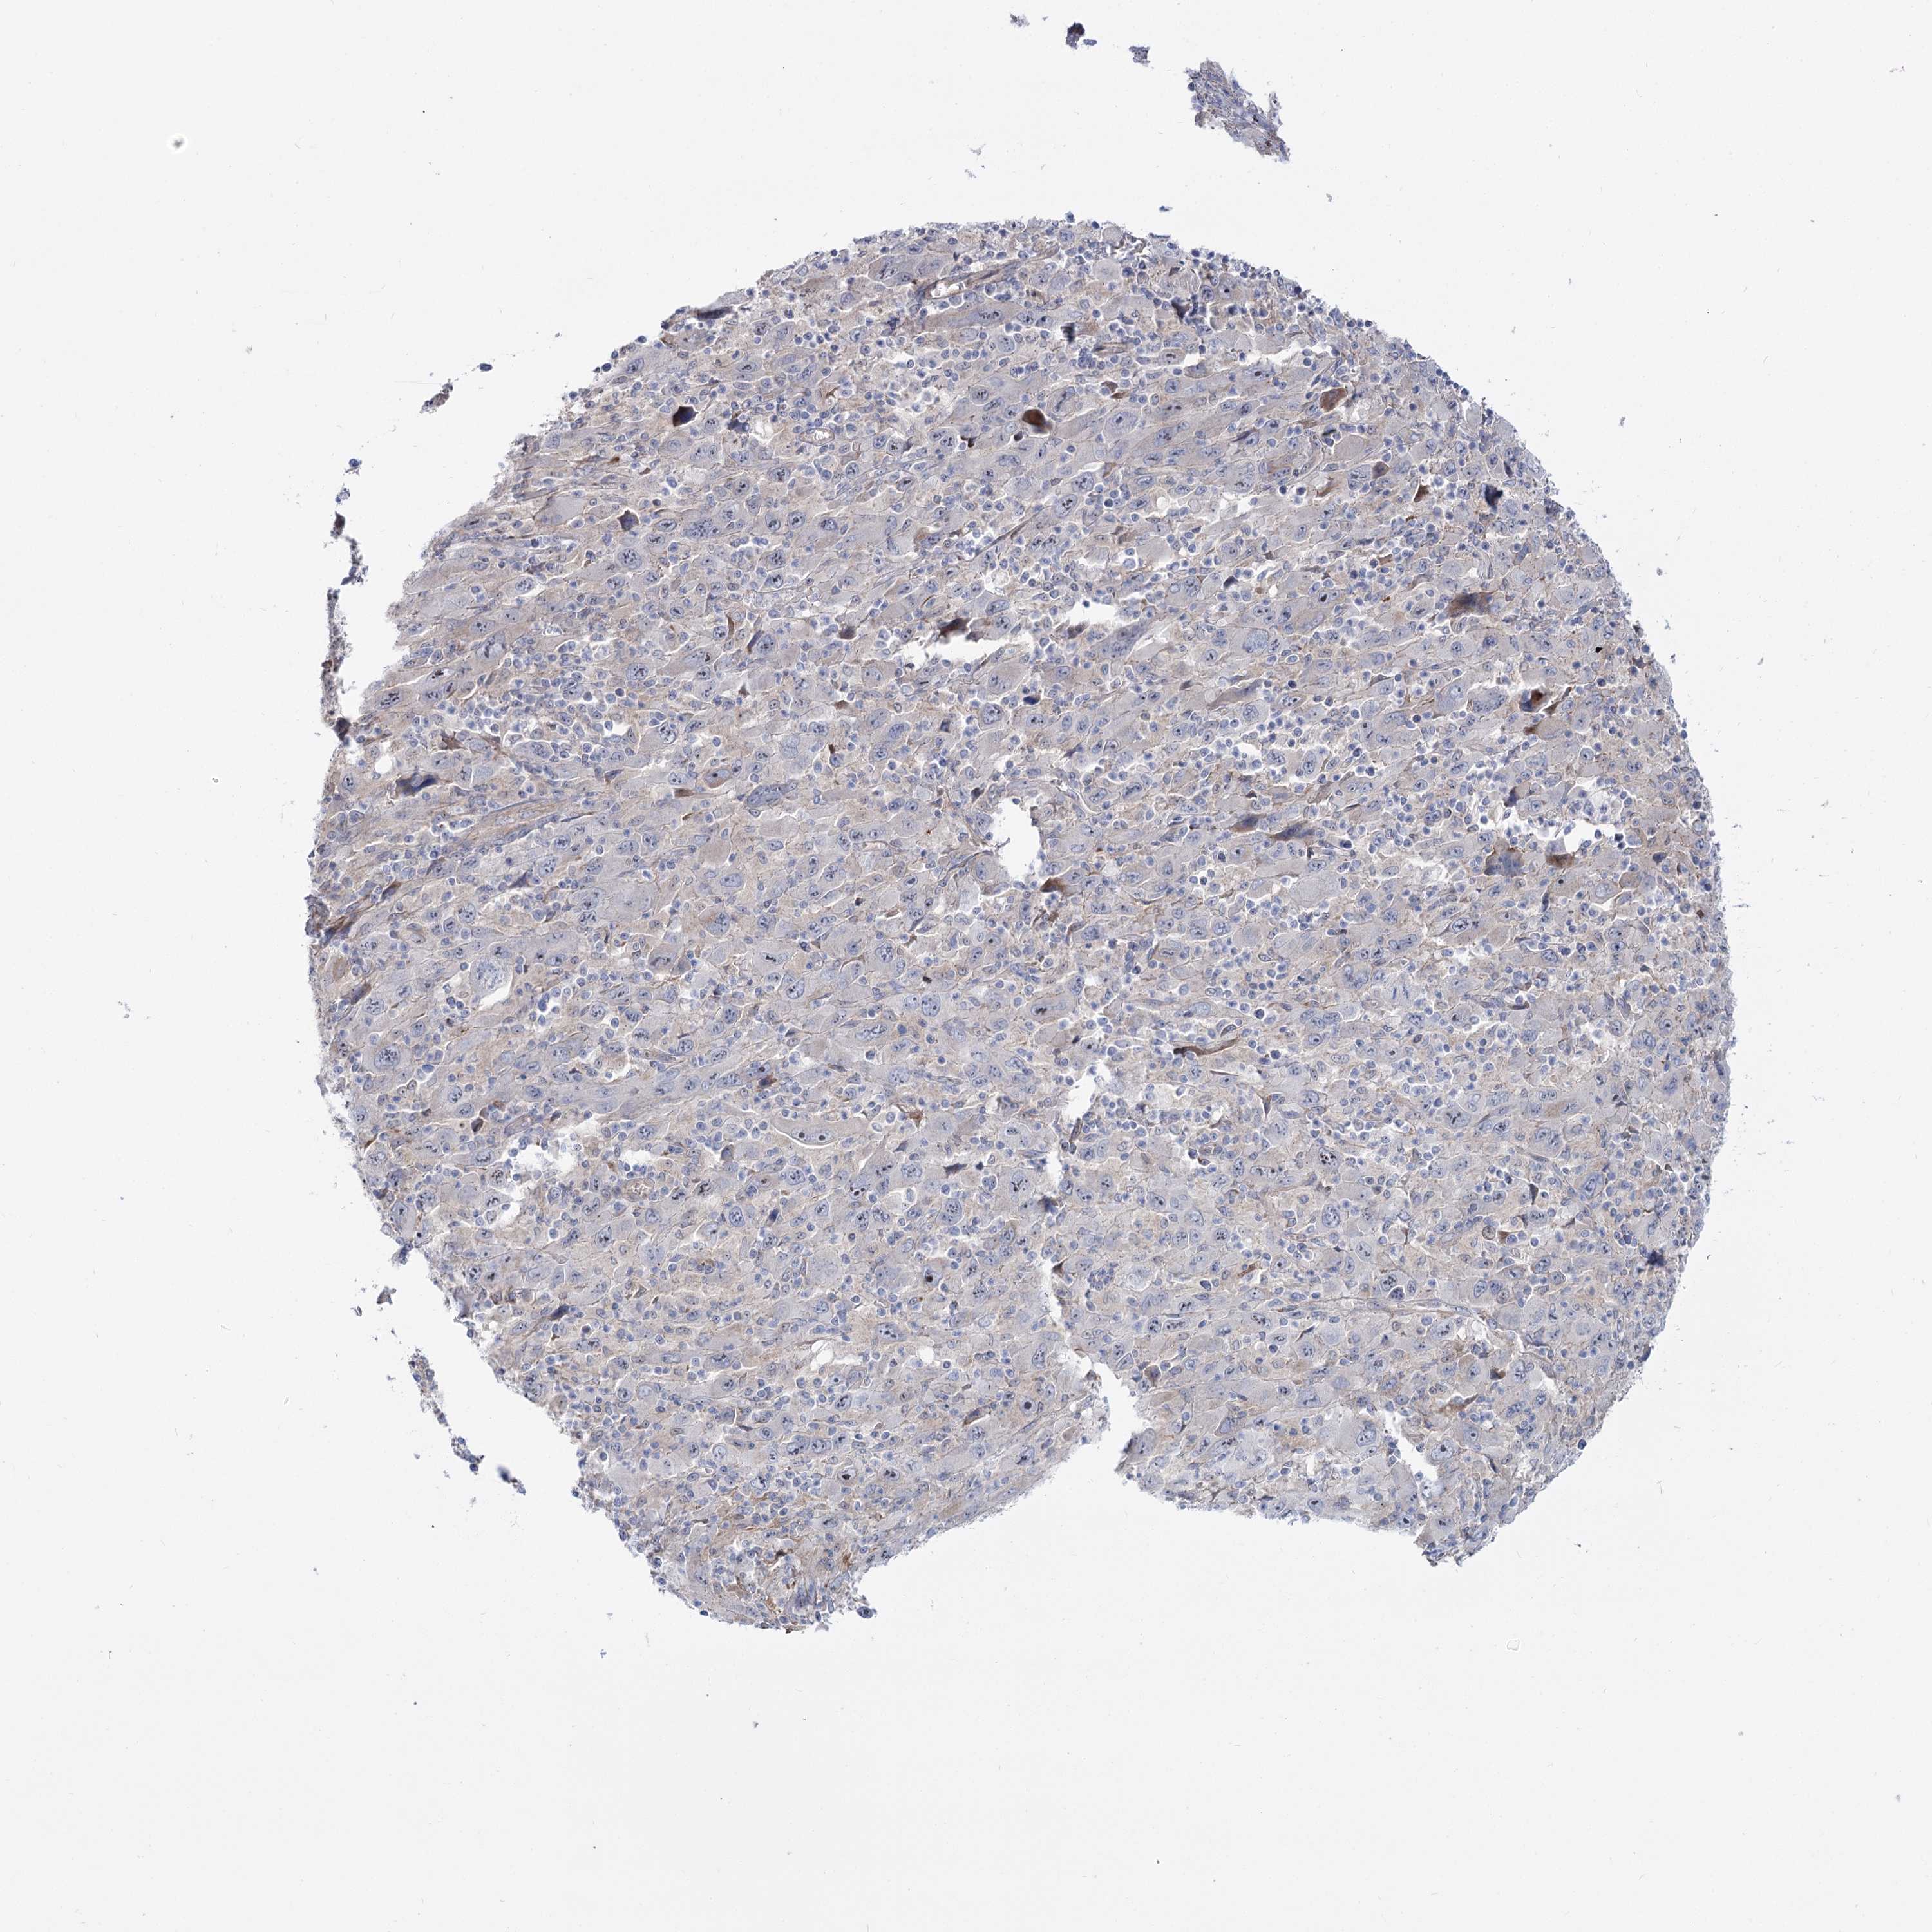

MELANOMA - Protein expressioni

A mouse-over function shows sample information and annotation data. Click on an image to view it in a full screen mode. Samples can be filtered based on level of antibody staining by selecting one or several of the following categories: high, medium, low and not detected. The assay and annotation is described here.

Note that samples used for immunohistochemistry by the Human Protein Atlas do not correspond to samples in the TCGA dataset.

Antibody stainingi

Antibody staining in the annotated cell types in the current human tissue is reported as not detected, low, medium, or high, based on conventional immunohistochemistry profiling in selected tissues. This score is based on the combination of the staining intensity and fraction of stained cells.

Each image is clickable and will lead to virtual microscopy that enables deeper exploration of all samples and also displays staining intensity scores, fraction scores and subcellular localization as well as patient and tissue information for each sample.

Antibody HPA038208

Antibody HPA038209

Staining

High

Medium

Low

Not detected

Intensity

Strong

Moderate

Weak

Negative

Quantity

>75%

75%-25%

<25%

None

Location

Nuclear

Cytoplasmic/membranous

Cytoplasmic/membranous,nuclear

Malignant melanoma, NOS

Malignant melanoma, Metastatic site